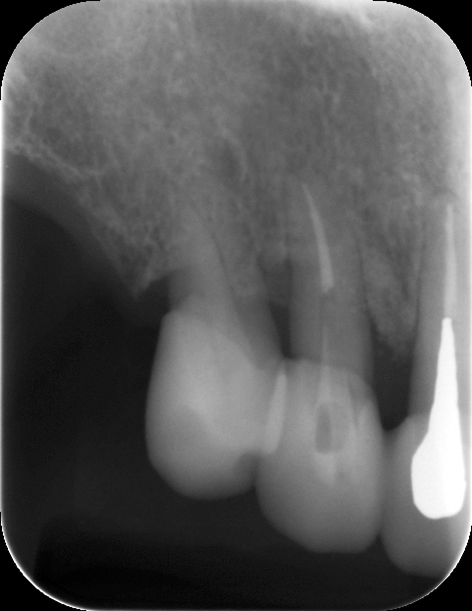

歯周病が進行すると、歯を支える骨が溶けて減少していきます。外から見えない骨の状態を評価するためには、X線検査を行います。当院では、X線検査に「CT」を使用しています。一般的には「レントゲン」と呼ばれるX線検査が知られていますが、二次元の画像を取得するレントゲンに比べて、CTはお口の周囲からの立体的かつ鮮明な映像を撮影することができます。

奥歯は根が複数に分かれていますが、歯周病が進行すると根の周囲の骨が溶けてしまい、根の分かれ目が露出してそこに歯垢や歯石が付着します。通常の器具ではこの部分に届かず、溜まった歯石を取り除くことができません。

そこで、「ルートセパレーション」という治療法を用い、歯を2~3に分割して掃除しやすくします。歯石や汚れを取り除いた後、被せ物を装着して見た目や機能性を回復させます。